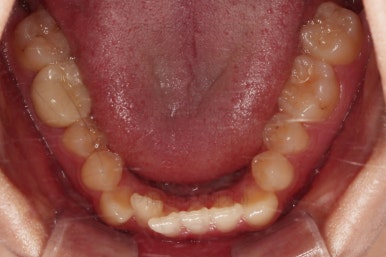

가벼운 철사에서 두꺼운 철사로 주기적으로 바꿔감에 따라 치열이 점점 가지런해지고 있습니다.

현재 모습도 나쁘지 않지만 좀 더 디테일을 맞춰주기 위해서 고무줄도 끼고, 왜소치 때문에 생기는 사이즈 부조화문제로 정중선이 안맞는 점은 일정 부분 수용하면서도 최대한 맞춰보기로 했습니다.

왜소치가 있어서 중앙선과 교합을 맞추는데 약간의 애로사항이 있었지만 최대한 잘 마무리를 하였습니다.

앞니 각도, 가지런한 느낌, 덧니 등 모든 점이 다 개선되었네요.

입안의 모습에서도 모든게 다 좋아졌고요.